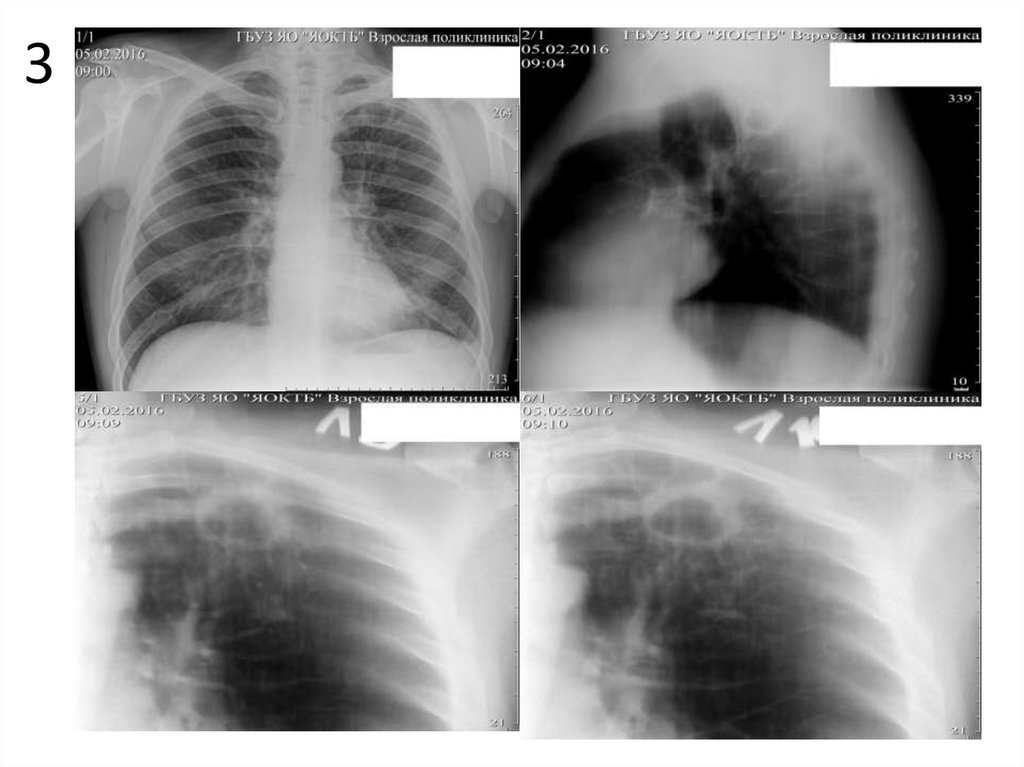

3